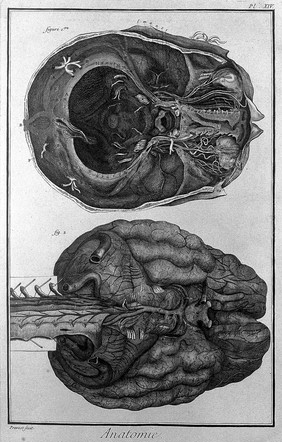

The anatomy of the brain : containing its mechanism and physiology : together with some new discoveries and corrections of ancient and modern authors upon that subject : to which is annex'd a particular account of animal functions and muscular motion : the whole illustrated with elegant sculptures after the life by H. Ridley.

Ridley, Humphrey, 1653-1708Date: 1695

The brain, after Haller and Ridley. Engraving by Prevost, 1762.

The brain, after Haller and Ridley. Engraving, 18th century.

The brain, after Haller and Ridley. Engraving by Benard, late 18th century.